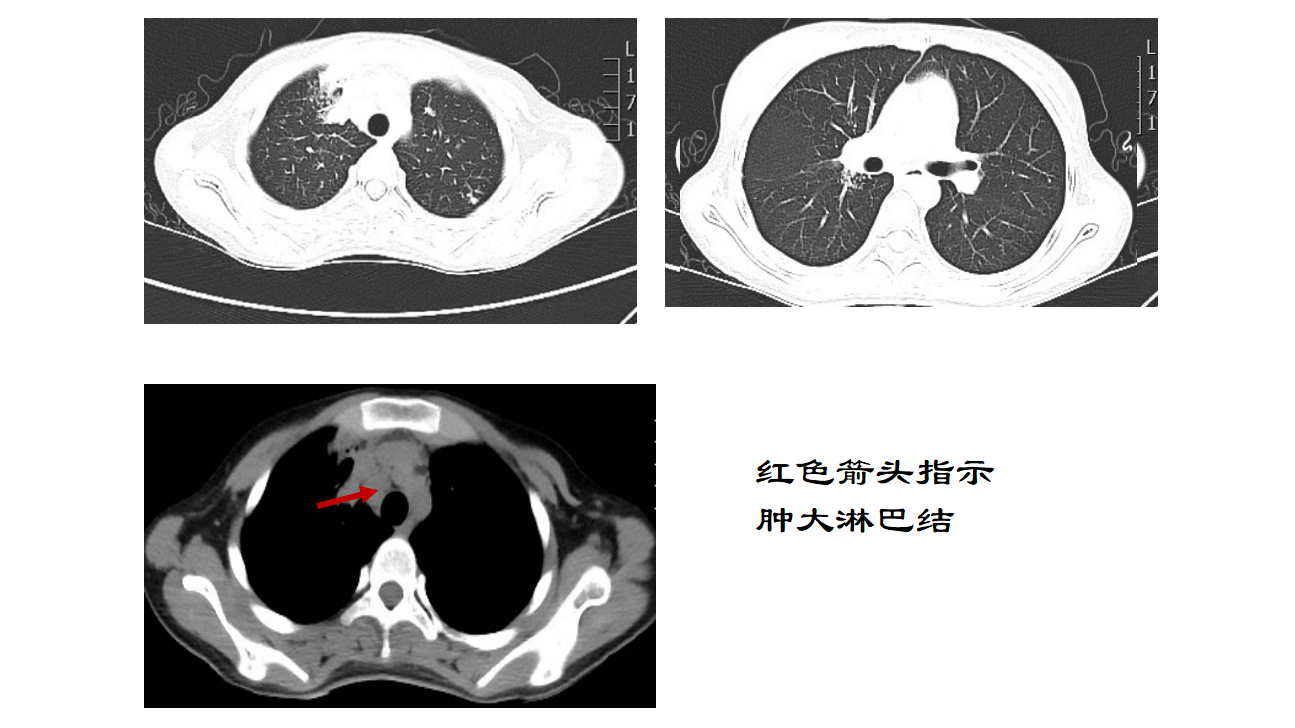

拨开云雾——以发热为主要表现的儿童多器官感染1例

2025儿科最佳临床实践天津市儿童医院呼吸科团队分享主讲嘉宾:李小乐 副主任医师点评嘉宾:宁静 主任医师天津市儿童医院呼吸科建立于上世纪五十年代,在全国儿科界率先引进脉冲震荡技术肺功能技术,率先完成了天津地区3~14岁儿童IOS正常值的测定,连续举办国家级继续教育项目,通气功能和气道反应性的检测水平居于全国领先水平,为天津地区儿童肺功能考核培训单位。呼吸科是全市定点诊治儿童结核病的科室,与天津市结核病控制中心密切协作,承担了各级结核病培训、宣教工作,参与制定多项儿童结核病的诊疗指南和行业标准,小儿结核病随访制度延续至今。